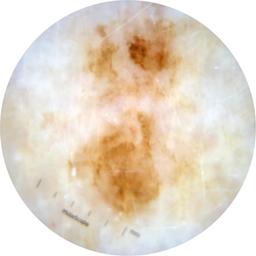

ISIC_2585736

Clinical

Field Value

acquisition_day 309

age_approx 75

anatom_site_1 Lower extremity

anatom_site_general lower extremity

concomitant_biopsy False

diagnosis_1 Benign

diagnosis_confirm_type single image expert consensus

family_hx_mm True

image_manipulation instrument only

image_type dermoscopic

lesion_id IL_4029789

patient_id IP_1553014

personal_hx_mm True

sex female